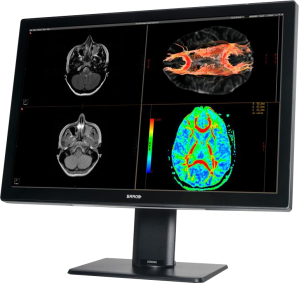

Kompaktne kirjeldav meditsiinimonitor on seade DICOM-standardile vastavate failide esitamiseks PACS-süsteemist, et tõlgendada meditsiinilisi kujutisi. Üldiselt on need diagnostilised monitorid, mis taasesitavad kõige täpsemal viisil igasuguste diagnostikaseadmete kujutiste üksikasju. Need on nii ühevärvilised kui ka värvilised meditsiinilised monitorid maatriksitega 1 MP kuni 5 MP, ühe või kahe monitori konfiguratsioonis ja 4 MP, 6 MP, 8 MP, 12 MP ühe paneeli konfiguratsioonis. Viimastel aastatel oleme näinud tugevat suundumust monokroomsete monitoride asendamisel värviliste monitoridega, mis võimaldavad kuvada pilte paljudest erinevatest viisidest, samuti traditsiooniliste kahe monitoriga jaamade asendamist ühe meditsiinilise monitoriga, millel on kõrge (ekvivalentne) eraldusvõime, mis tagab kõrgeim pildikvaliteet vastavalt DICOM standardile.

Olles teadlik, et kirjeldavad monitorid (kogu kirjeldavad jaamad) on diagnostikaprotsessi kriitiliseks lüliks, varustavad tootjad monitore mitmete lisafunktsioonidega, mis reguleerivad ja korrigeerivad automaatselt pildiparameetreid. See annab kindlustunde õiges diagnoosis ja vabastab radioloogid vajadusest teostada pidevat seadmete kontrollimist. DICOM standardile vastav meditsiiniline monitor võimaldab õigeks diagnoosimiseks vajaliku pildi täpset kuvamist, tagades samas ühilduvuse teiste seadmetega.

Mammograafiline diagnostika nõuab detailide võimalikult täpset taasesitamist nii ekraani eraldusvõime kui pildikvaliteedi osas. Seetõttu kasutatakse siin kahe/mitme monitoriga süsteemides 5 MP/6 MP monitore ja ühe monitoriga süsteemides 12 MP monitore. Need on varustatud uusimate ja arenenumate tehnoloogiliste lahendustega, mis kontrollivad pidevalt pildiparameetreid võimalikult suure täpsusega. Seetõttu saab neid monitore kasutada kõigi tehtud uuringute kirjeldamiseks (multimodaalsuse monitor).

Hoolimata mitte eriti nõudlikest nõuetest CT- ja angiograafiamonitoride kujutise parameetritele, pakuvad meditsiiniseadmete tootjad palju arenenumaid lahendusi, mis võimaldavad palju detailsemat pildianalüüsi, kiiremat diagnoosimist ja paremat töömugavust. See on kooskõlas ka suundumusega kasutada monitore paljude erinevate meetodite uuringute kirjeldamiseks. Kavandatavate monitoride diagonaali suurus on 21,5-27 tolli ja eraldusvõime 2 MPix kuni 8 MPix. Nad suudavad kuvada nii värvilisi kui ka ühevärvilisi pilte, mis vastavad DICOMi osale 14. Mõnel neist on sisseehitatud spetsiaalsed andurid, mis kontrollivad automaatselt pildiparameetreid. See tagab õige pildi kuvamise ja täpse diagnoosi.